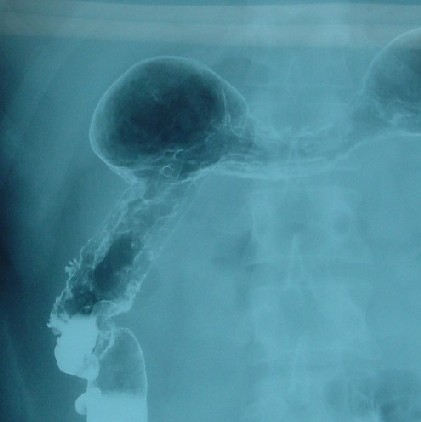

2004年01月16日 注腸検査